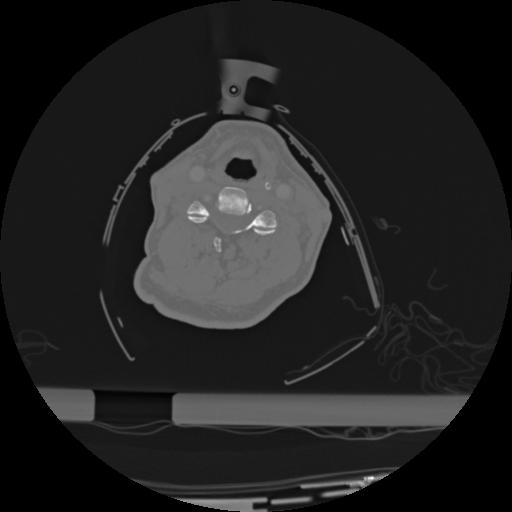

22 ANGIO,CE,Vol,0.5,ANGIO,,